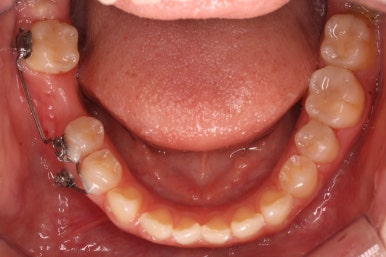

불과 4개월만에 장리가 충분히 확보된 모습입니다.

측면에서 본 모습입니다.

자리가 점점 넓어지는 것이 보입니다.

키다리아저씨치과에서는 부산부분교정을 통해 어금니가 충분히 뒤로 이동을 하면서 공간이 확보 되었다고 생각되면 임플란트 식립이 완료가 될 때까지 유지를 해줍니다. 유지가 원활히 되지 않으면 임플란트가 최종 완성되는 몇 개월간 다시 쓰러질 수 있거나 위치가 변할 수 있기 때문이죠.